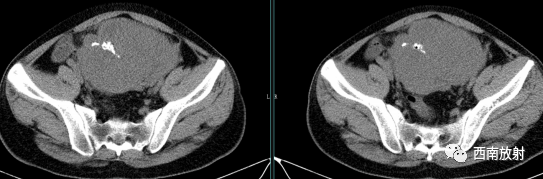

▲小肠间质瘤,肿块巨大,超过10cm,实质内见多发钙化灶;

▲小肠间质瘤,肿块巨大,超过10cm,实质内见多发钙化灶;动脉期肿块不均匀强化,见斑片状坏死区及环状或花边状改变[4]。

▲小肠间质瘤,肿块巨大,超过10cm,实质内见多发钙化灶;动脉期肿块不均匀强化,见斑片状坏死区及环状或花边状改变。静脉期强化更加明显。

▲小肠间质瘤,高度危险性。肿块术中所见。肉眼所见,腹腔肿物:灰白肿物1个与一段小肠相粘连,肿物大小15*13*10CM,表面光滑,切面灰白质脆,小肠长14CM,直径3CM,与肿物相粘连长6CM,肠腔未见肿物及溃疡。